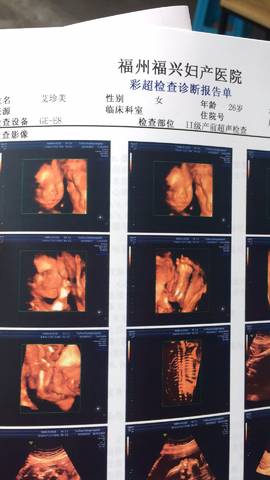

双顶径是有点小,我22周5去做的时候,双顶径58,股骨长41 展开阅读全文

那是小了 我22周的时候双顶径57mm 股骨长37mm

23周,医生说偏小几天

我b超显示的是22周5

我23周,B超显示才22周4

恭喜宝妈!接四维大排畸顺利通过!

接四维排畸顺利通过!!!

偏小一点医生也没说有事,他说小孩偏小几天

后面应该能长上去的

双顶径是有点小,我22周5去做的时候,双顶径58,股骨长41